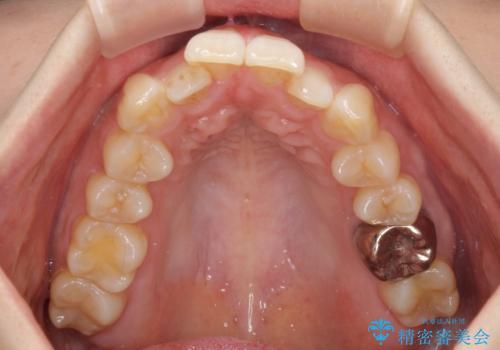

- 前歯のデコボコを気にして来院された患者様です。

非抜歯矯正にて治療を行うと、仕上がりで口元が突出する可能性があったため、小臼歯抜歯での矯正治療を行うこととしました。

上顎は左右の第一小臼歯2本を、下顎は左右の第二小臼歯2本を抜歯して、口元が突出しないようにしながら、奥歯の咬み合わせを改善していく治療計画としました。